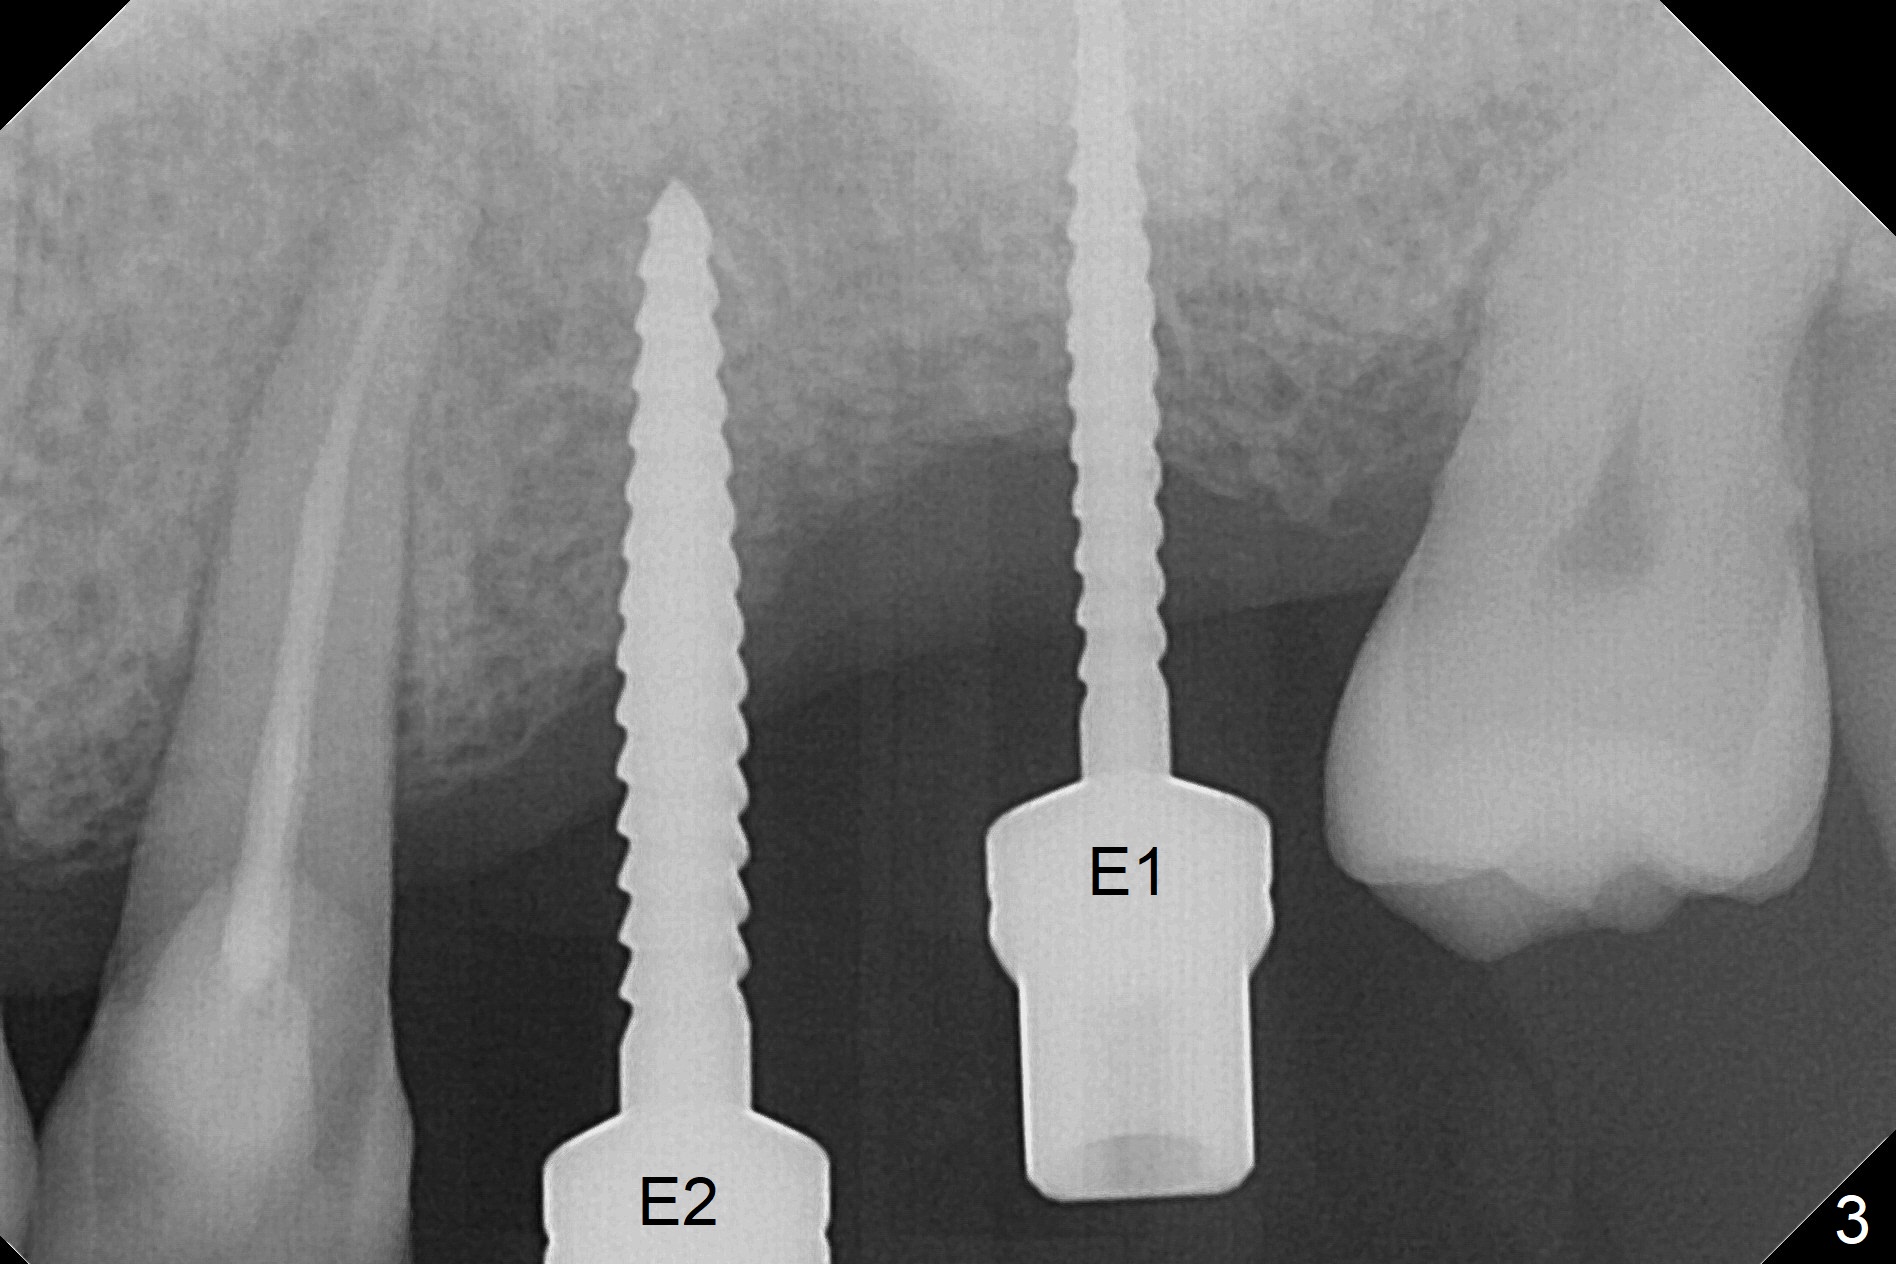

When 1.2 mm drill is used for osteotomy at #14 and 15, the bone feels to be soft (Fig.1). After change in trajectory (Fig.2), Expander 1 (Fig.3: E1, 1/1.6 mm) can be inserted at #14 and 15, while E2 (1.2/2.3 mm) cannot at full length at #14, suggesting hard bone. Osteotomy continues with drills until 4.1x14 mm, followed by insertion of E4 (2.4/3.7 mm) at #14, while osteotomy goes on until E3 (1.7/3.1 mm) at #15 (Fig.4). A 4.5x12 mm SM implant is placed with 50 Ncm (with insertion of a 5.8x4(2) mm abutment as a guide for #15 osteotomy, Fig.5). The apical portion of the osteotomy at #15 (Fig.5 red line) is finished with drills, leading to placement of a 4.5x12 mm implant (>50 Ncm) and 4.8x4(2) mm abutment (Fig.6). With bone density is more than 200 units, bone expansion appears to be not indicated. The patient returns for #13-15 crown prep 4.5 months postop (Fig.7). Abutments change to 5.8x5(3) and 5.8x4(3) mm at #14 and 15, respectively with mesial reduction of the tooth #16 (curved line) before impression. Minimal bone loss is observed 1 year 5 month post cementation (Fig.8,9), thanks to pre-existing wide bone.